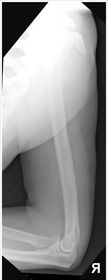

| AP Forearm | not AP - wrist is internally rotated, proximal radius and ulna are superimposed |

| Lateral Forearm | Elbow is not 90 degrees proximal radius and ulna are superimposed |

| AP Forearm | ANATOMY: entire forearm: wrist joint -> elbow joint CRITERIA: slight superimposition of proximal radius/ulna POSITIONING: CR perpendicular @ midforearm |

| Lateral Forearm | ANATOMY: entire forearm including wrist joint and elbow joint CRITERIA: humeral epicondyles must be superimposed distal radius/ulna superimposed half of radial head superimposed by coronoid process olecranon process in profile POSITIONING: CR perpendicular @ midforearm |